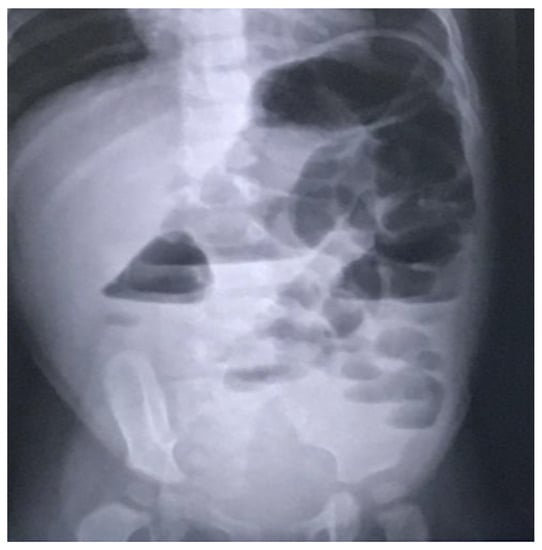

Following an abdominal computed tomography (CT) scan, an abdominal ultrasound revealed a calcified mass approximately 6/4 cm in diameter anterior to the L1–L4 lumbar spine and aorta but not in contact with the left kidney. There were no anomalies in the pancreas (Figure 2).

Figure 2.

Retroperitoneal tumor with calcifications, as shown on a CT scan.